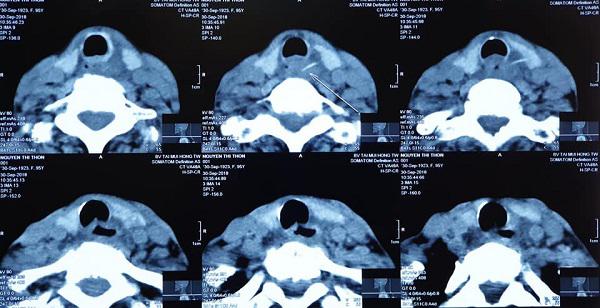

BS Thắng cho biết, kết quả chụp phim bệnh nhân cho thấy, bệnh nhân có dị vật (xương cá) đâm xuyên từ lòng thực quản ra vùng cổ, ngay sau đó bệnh nhân được các bác sĩ BV TMH Trung ương mở cạnh cổ lấy dị vật.

Hình ảnh bệnh nhân hóc xương cá và sau khi được lấy ra.

Do quá đau đớn, bà Ph. có ra bệnh viện tỉnh thăm khám, sau đó được chuyển xuống Bệnh viện Tai Mũi Họng Trung ương. Tại đây, bệnh nhân đã được chụp phim CT và nghi ngờ có dị vật trong thành thực quản, bệnh nhân đã được nội soi thực quản ống cứng, nhưng không phát hiện ra dị vật và các bác sỹ đã phải mở cạnh cổ kiểm tra và phát hiện 3 mảnh xương gà, mảnh dài nhất 3cm trong thành thực quản.

Hình ảnh chụp chiếu phát hiện có dị vật trong thanh quản.